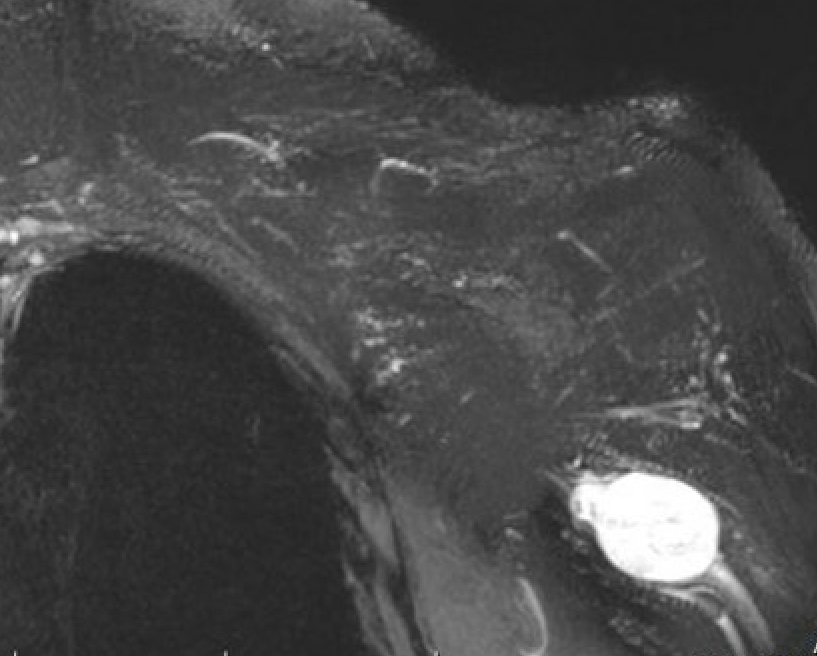

MRI

Target sign

- hypointense centrally

- hyperintense peripherally

Neurofibroma brachial plexus